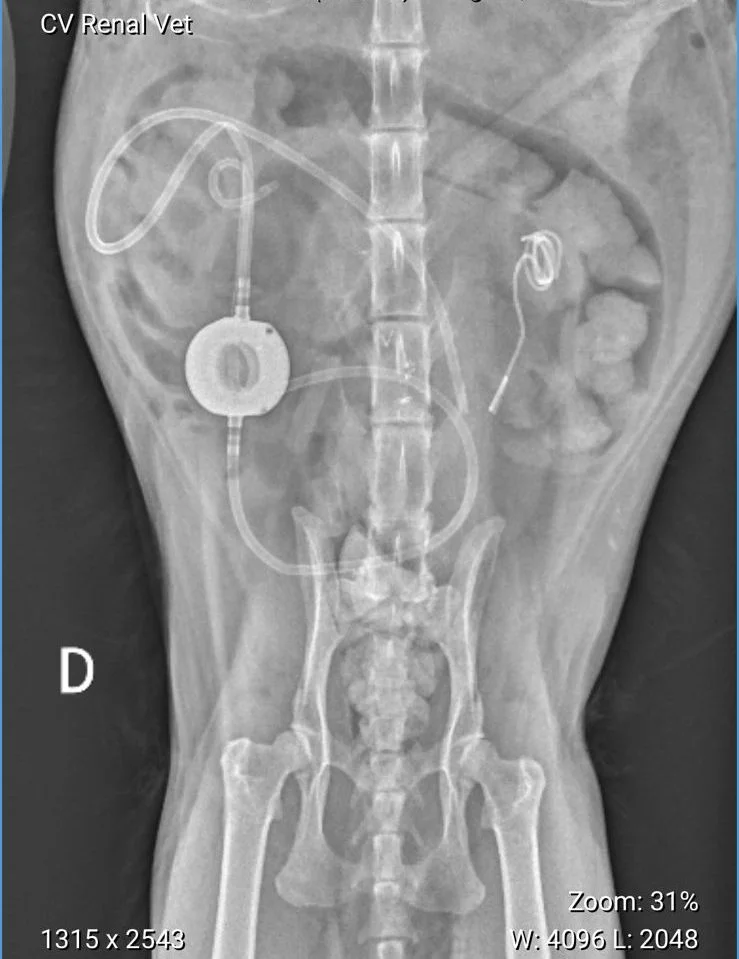

Comparação entre BY PASS ( à esquerda da imagem) e CATETER DUPLO J (à direita da foto)

Qual é mais fisiológico? Qual é menos traumático? Qual causa menos complicações?